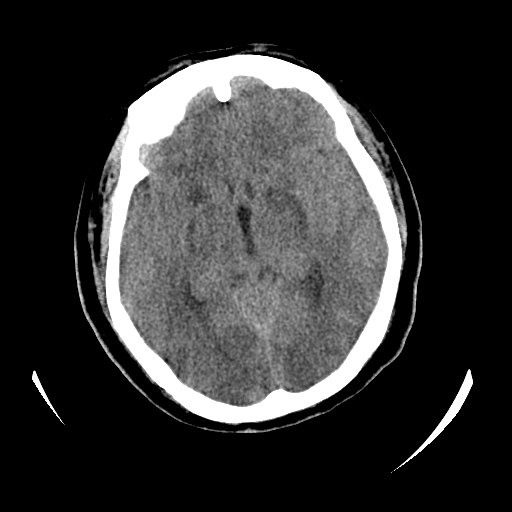

女,53岁,发现昏迷1天,血压不高,有精神病史。临床诊断:脑梗死?

ct诊断:1、双侧基底节区对称性脑梗塞。

2、双侧额叶、枕叶广泛密度减低,考虑缺血梗塞可能性大。

3、脑池小,脑沟浅,提示颅内高压。

测左枕叶白质ct值 约22hu 。请各位老师给出恬当诊断。

征象:病变呈对称性分布于双侧大脑半球,累及范围广泛,白质较灰质密度减低更为明显;脑沟变浅,脑池变窄;

缺氧性脑梗死的影像表现比较特殊:

由于苍白球对血供的敏感度较高,故较早受累;其它的表现有分水岭区脑梗死等;